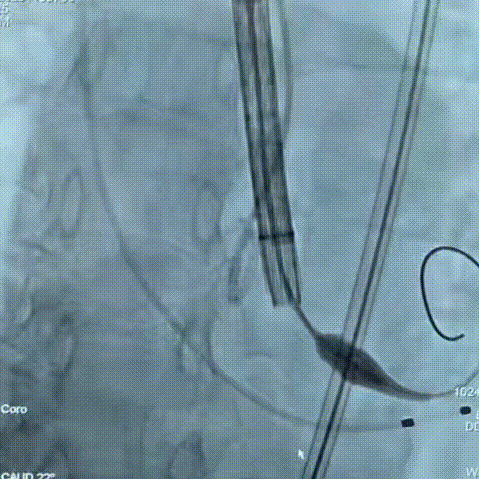

手术过程

手术过程:在右股动脉穿刺建立通路后,顺利送入大鞘,经食道超声及血管造影确认路径稳定。18mm球囊预扩后评估冠脉灌注良好,后将Prostyle A® AV26瓣膜精准释放于目标位置,超声显示无瓣周漏,术后即刻造影显示无明显反流,术前PGmean40mmHg,术后导管测平均跨瓣压差8mmHg,心功能明显改善,患者生命体征平稳。

主动脉根部造影

定位

迅速锚定